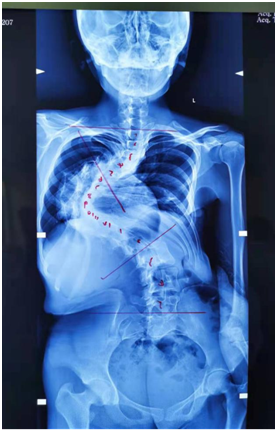

来到郑州院区后,小潘妈妈的心情从忐忑不安到充满希望。她说从没想到有那么多和小潘相似的孩子能够“重生”,本以为这一辈子不会再有希望了。见到周献伟副主任之前治愈的病例,小潘和妈妈都信心百倍。周献伟副主任在细致看过小潘的脊柱情况后,与家属进行了沟通,最后做出了先牵引再手术的决定。

小潘的牵引经历了两个过程,首先坐在椅子上,初期的牵引让小潘承受了很多痛苦,可是牵引的效果颇为明显,这就让她更有信心坚持下去。后期在床上的牵引,小潘很快就适应了,急切做手术的心情随着牵引的日渐好转变得越发迫切。小潘的主治医生刘玉峰大夫介绍;通过重力和骨牵引能够让有活动度的关节和软组织得到松解,这样手术做起来就会更加安全。

经历了一个月的牵引,终于在4月19日早上,小潘进了手术室。周献伟副主任依然为小潘打气:“打完麻药,剩下就交给我了,醒来你就会长高的!”小潘再一次坚强地点点头。手术经历了差不多5个多小时,当小潘被推出来的时候,小潘妈妈明显地感觉到小潘像被拉直了一样,挺起来了!手术后据实际测量,小潘长高了10厘米!在7楼护理单元吴春丽护士长的带领下对小潘进行精心的术后康复护理。经过康复锻炼,小潘恢复得很快。